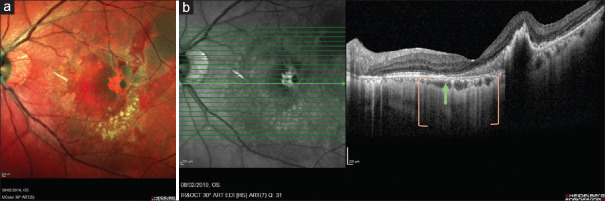

This report describes a patient with polypoidal choroidal vasculopathy (PCV) with fovea-involving retinal pigment epithelium (RPE) tear that showed tissue remodeling with a good visual outcome. Imaging over the patient's clinical course from 2019 was reviewed. A 74-year-old female presented with left submacular hemorrhage and a large multi-lobular pigment epithelial detachment. Left eye vision was 6/19 at the presentation. Indocyanine green angiography (ICGA) revealed underlying PCV. One month after initiation of intravitreal aflibercept (IVA, Bayer), she developed fresh subretinal hemorrhage. An RPE tear of 1 disc area in size, centered over the fovea was diagnosed. The torn RPE edge was scrolled up temporal to the fovea on spectral-domain optical coherence tomography (SD-OCT), with hypertransmission into the choroid observed over the area of RPE loss. Left eye vision after the RPE tear was 6/15. Over the next 2 months, the subretinal hemorrhage resolved following further IVA. At month 3, fundus autofluorescence (FAF) demonstrated hypo-autofluorescence while fundus fluorescein angiography (FFA) and ICGA showed a window defect corresponding to the area of RPE tear. On SD-OCT, there was a faint hyper-reflective layer where one might expect the RPE layer to be. Serial SD-OCT scans over 5 years revealed increasing prominence of the hyperreflective layer between the ellipsoid zone and Bruch's membrane. FAF remained hypo-autofluorescent. At the last review, the patient retained 6/9 vision. We report a case of fovea-involving RPE tear documented with multimodal imaging with good visual outcome, which is atypical. Serial OCT suggests tissue remodeling may explain the functional preservation.